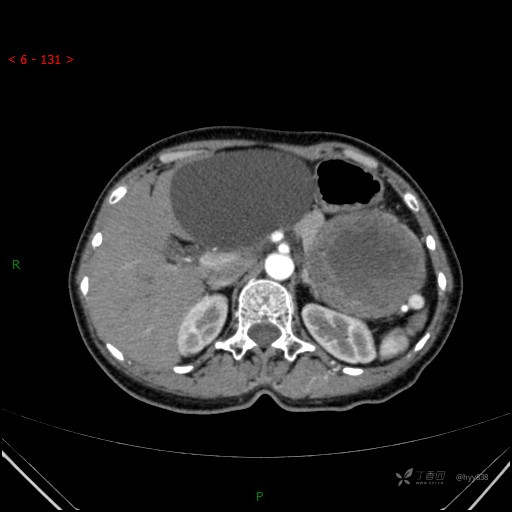

腹部CT平扫